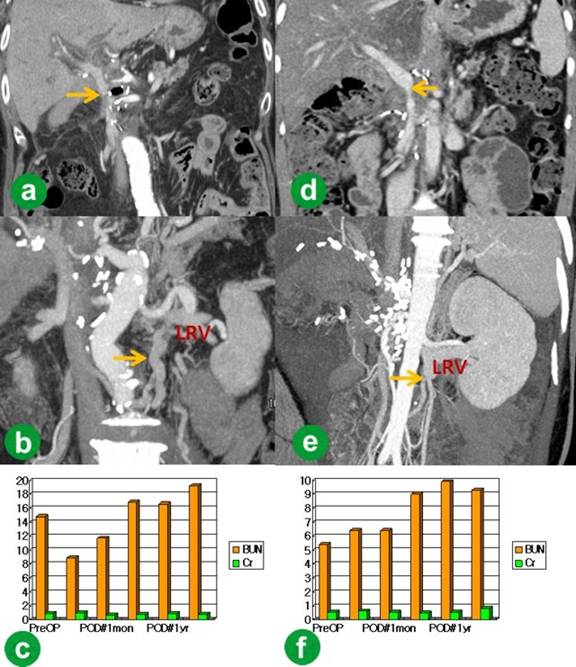

The pathologic report confirmed a ductal adenocarcinoma of the pancreas and complete R0 resection. He had delayed gastric emptying during the postoperative period, but this was resolved with conservative management. A follow-up CT demonstrated a patent graft (Figure 3a), good collateral flow and a well-perfused left kidney (Figure 3b). Postoperative follow-up serum creatinine levels were maintained within the normal range (varing between 0.60 and 1.16 mg/dL; reference range: 0-50-1.40 mg/dL) (Figure 3c). Renal function preservation was verified by the development of collaterals on follow-up CT. He was revealed to have multiple liver metastasis 19 months after the operation, and died after 21 months.

Figure 3. Follow-up of Cases #1 and #2. a. CT of Case #1 demonstrating a patent portal flow (arrow). b. CT of Case #1 showing development of collaterals (arrow) and a well-perfused left kidney. c. Postoperative follow-up serum creatinine levels of Case #1 were maintained within the normal range. d. CT of Case #2 showing a patent portal flow (arrow). e. CT of Case #2 revealing well-developed collaterals (arrow) and good perfusion of the left kidney. f. The postoperative follow-up serum creatinine levels of Case #2 were maintained within the normal range. Cr: creatinine; BUN: blood urea nitrogen; LRV: left renal vein; POD#1mon: 1-month postoperative; POD#1yr: 1-year postoperative; PreOP: preoperative |

The histopathological examination of the en bloc specimen disclosed a ductal adenocarcinoma of the pancreas and an R0 resection. She was discharged on the 16th operative day after an uneventful recovery. A follow-up CT scan one month postoperatively also showed a patent graft (Figure 3d), good collateral flow and a well-perfused left kidney (Figure 3e). Postoperative follow-up serum creatinine levels were maintained within the normal range (between 0.33 and 0.86 mg/dL) (Figure 3f). She showed no evidence of recurrence at her last follow-up (23 months postoperatively).

Options for a venous conduit for reconstruction after superior mesenteric-splenic-portal vein confluence resection include prosthetic, autologous or cryopreserved cadaveric vein grafts. Despite its ready availability and valid size match, the use of a prosthetic graft such as polytetrafluoroethylene (PTFE) is not indicated due to the potential risk of infection and thrombosis [16]. The portal vein has medium velocity but a high volume flow. Therefore, some reports have demonstrated that the use of PTFE interposition grafts did not increase the risk of thrombosis [17]. However, Smoot et al. [18] reported a higher percentage of thrombosis in PTFE grafts, and they changed to the left renal vein as the preferred conduit. As for selecting potential autologous grafts for the superior mesenteric-splenic-portal, the internal jugular, femoral, great saphenous, gonadal, common iliac, external iliac and splenic veins are all candidates [8, 11, 12, 16, 19]. However, the great saphenous and gonadal veins have a size disparity which requires some modification to be applied as a portal vein graft. Therefore, these veins cannot be used in the same way as the internal jugular vein and the others listed above. Furthermore, harvesting these autologous veins requires creating an additional wound and is associated with other postoperative complications, such as lymphedema and venous thrombosis. From this point of view, the left renal vein has several advantages, such as suitable length, comparable caliber to superior mesenteric-splenic-portal vein confluence, easy accessibility during pancreaticoduodenectomy and the fact that it is a safe procedure [9, 10, 11, 12, 20]. Furthermore, all routes for central venous access can be maintained when using the left renal vein, which is especially important in patients who have undergone a major operation such as a pancreaticoduodenectomy. Left renal vein grafting is also justified because the left renal vein has various collateral branches, such as the inferior phrenic and adrenal tributaries, the gonadal vein, renal-azygos communication, and splenorenal communication; therefore, there is no deterioration of renal function after harvesting the left renal vein [10, 12, 20, 21]. The follow-up CT in our cases clearly showed that the development of collaterals enabled the preservation of the renal function. The segment of the left renal vein can be extended onto the portion just distal to the renal-azygos branch to preserve the gonadal and renal-azygos venous drainage essential for preservation of the renal function [9, 22]. This usually provides a segment of about 3-4 cm in length of renal vein graft [10, 11]. Harvesting of the graft and resection of the involved segment of the superior mesenteric-splenic-portal vein confluence should follow the completion of the dissection of the retroperitoneal margin so as to properly assess the need for interposition grafting and minimize the clamping time of the portal flow. In our cases, left renal vein resection did not increase the serum creatinine level during long-term follow-up, and the graft patency and well-maintained collateral flow was confirmed by follow-up radiologic images. The patients’ survival outcome was acceptable.